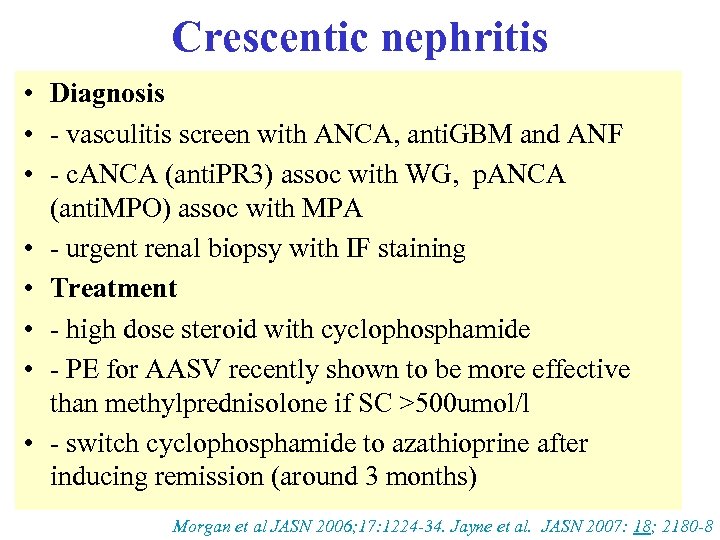

Crescentic nephritis • Diagnosis • - vasculitis screen with ANCA, anti. GBM and ANF • - c. ANCA (anti. PR 3) assoc with WG, p. ANCA (anti. MPO) assoc with MPA • - urgent renal biopsy with IF staining • Treatment • - high dose steroid with cyclophosphamide • - PE for AASV recently shown to be more effective than methylprednisolone if SC >500 umol/l • - switch cyclophosphamide to azathioprine after inducing remission (around 3 months) Morgan et al JASN 2006; 17: 1224 -34. Jayne et al. JASN 2007: 18; 2180 -8

Crescentic nephritis • Diagnosis • - vasculitis screen with ANCA, anti. GBM and ANF • - c. ANCA (anti. PR 3) assoc with WG, p. ANCA (anti. MPO) assoc with MPA • - urgent renal biopsy with IF staining • Treatment • - high dose steroid with cyclophosphamide • - PE for AASV recently shown to be more effective than methylprednisolone if SC >500 umol/l • - switch cyclophosphamide to azathioprine after inducing remission (around 3 months) Morgan et al JASN 2006; 17: 1224 -34. Jayne et al. JASN 2007: 18; 2180 -8